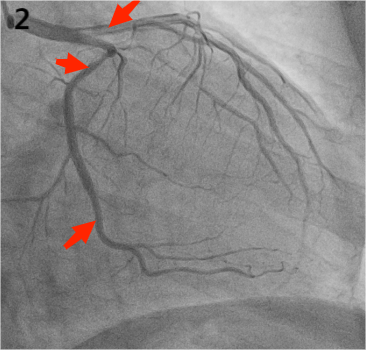

2月前杜大爷再次出现“烧心”就诊于漯河市中心医院消化科门诊,消化科黄德峰主任医师经过仔细的查体和诊断,考虑“冠脉综合征”可能,遂护送患者至漯河市中心医院心内科门诊行心电图示:III度房室传导阻滞,心率:35次/分。结合患者症状和发病时心电图,心内科二线陆振涛主任医师立即启动导管室,至心内科导管室行冠状动脉造影术,结果如下:

LM未见异常,前向血流TIMI-3级;LAD主支近段90%左右节段性狭窄,前向血流TIMI-3级;LAD中段70%左右节段性狭窄,前向血流TIMI-3级;LCX主支近段85%左右节段性狭窄,前向血流TIMI-3级;远段可见支架影,支架内血流通畅,前向血流TIMI-3级。(图1)